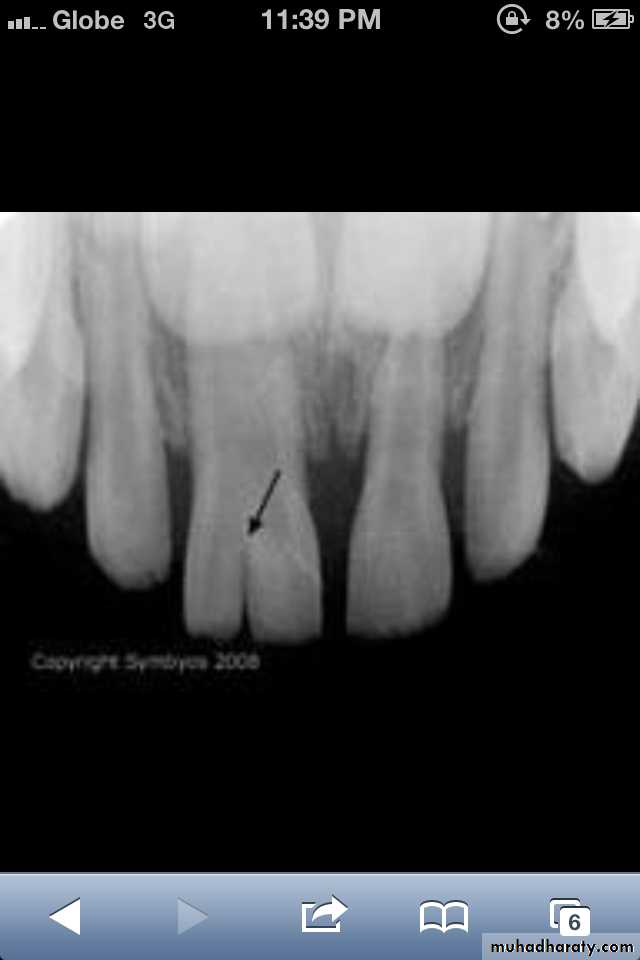

Dilaceration

*Dilaceration is a disturbance in tooth formation that produces a sharp bend or curve in the tooth (root or crown).

Dilaceration of the crown

specimenX-Ray

Dilacerated root. The apical portion of the root is bent buccally or lingually into the plane of the central ray. Note the halo in the apical region, produced by the PDL

space (arrow).